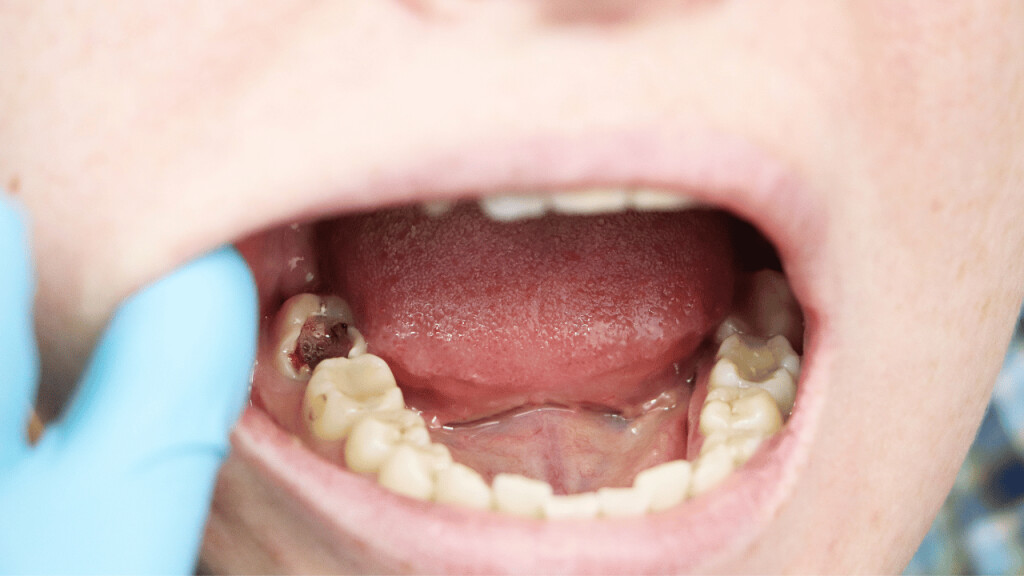

A loose tooth can be very annoying and discomforting. Your oral hygiene, gum disease, teeth grinding, hard food, mouth injury, anything can result in a loose tooth. You can let your tooth come out on its own. But the issues that come with that, like problems in eating food, constant sensitivity, etc can be hard to bear. And you just can’t keep waiting for your tooth to fall on its own for a long time. So, how to get a tooth out in a fast and painless way?

How to pull an adult tooth out without pain?

There are a few ways through which you can pull out a loose tooth without hurting yourself. However, if you are experiencing any kind of inflammation or pain, it is advisable that you visit a dentist.

These are a few ways to get a tooth out in fast and painless ways. But the process doesn’t stop here. Aftercare of your gum is very important.

Aftercare tips after pulling out a tooth

Pulling out a tooth can be quite painful and finding a little blood on the spot is common. Here are a few care tips after pulling out the loose tooth.

1. Use sterile gauze

Apply a little pressure on the tooth socket using sterile gauze to stop the bleeding. The bleeding should stop in a few minutes. You can also press it gently using the upper tooth.

4. Wait for 24 hours before rinsing

After pulling the tooth, there will be a blood clot in the tooth socket. This clot will help the area to heal properly hence it is vital to let it remain in place for 24 hours at least. So, wait for that time before rinsing your mouth. Use a straw to drink water and avoid anything that can result in suction or vigorous rinsing.